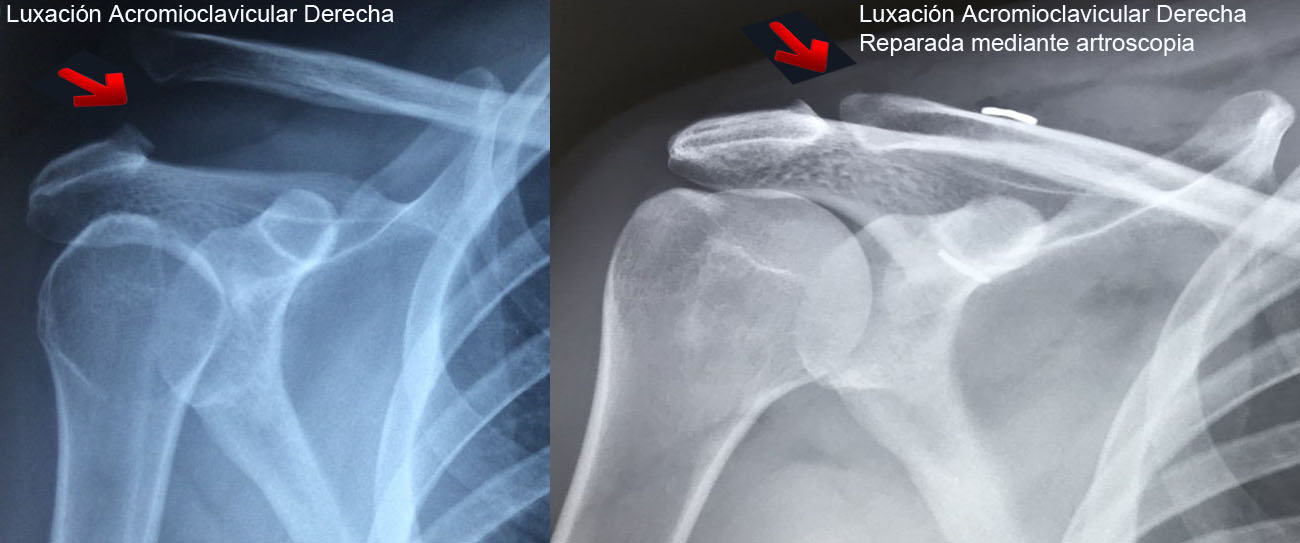

Artroscopia Hombro